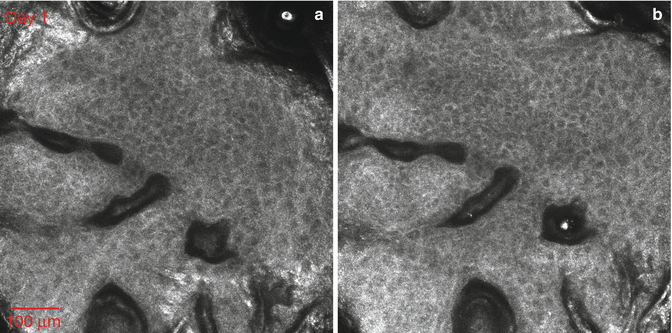

Fig. 26.1

Two confocal images obtained from the same skin site and from the same depth (approximately 80 μm) on Day 1 (a) and on Day 3 (b). Papillae and some keratinocytes loaded with melanin granules can be seen